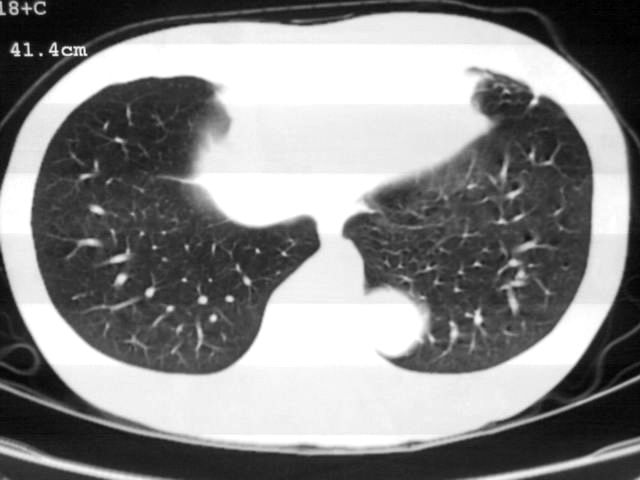

以下是引用苯小孩在2007-4-24 19:46:00的发言:[br]左下肺内侧基底段,见类圆形病灶,边缘清晰光滑.强化后轻中度强化.<平扫第4层面似有从腹主动脉相连血管影,可惜强化扫描这层没有抓住>考虑:左下肺隔离症.建议dsa或薄层强化重建观察.

以下是引用同在2007-4-24 20:11:00的发言:[br]考虑肺隔离症